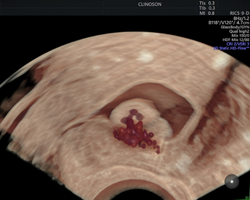

Apaixonado por diagnósticos precisos e tratamentos minimamente invasivos, sou especialista em exames avançados, como a avaliação da endometriose e o HyCoSy (Histerossonografia com Contraste), e também em tratamentos minimamente invasivos de miomas uterinos.

- Pioneiro na realização de HyCoSy – Histerossonossalpingografia com contraste de microbolhas em Porto Alegre

Investigando a infertilidade? Conheça o HyCoSy